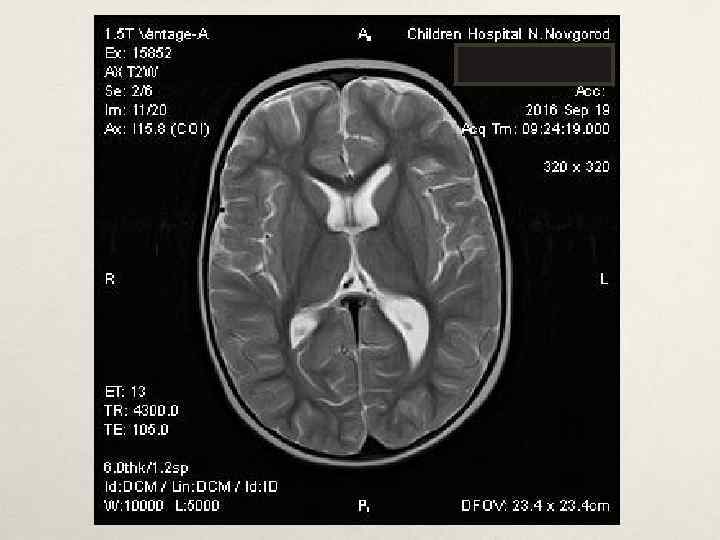

Клинический случай № 1 • В нейрохирургическом отделении: • МРТ головного мозга с КУ от 19. 05. 2016 – картина кистозно-солидного образования мозжечка, внутренняя окклюзионная гидроцефалия • Проведена операция – трепанация задней черепной ямки, удаление опухоли левой гемисферы мозжечка. Согласно гистологическому заключению и пересмотра препаратов в НИИ им. Бурденко – пилоидная астроцитома Grade I. МРТ головного мозга с КУ в динамике – остаточная опухоль 1. 7*1. 8*2. 3 см в левой гемисфере мозжечка. • • • В лечении: диакарб, аспаркам, дексазон, цефтриаксон, этамзилат, глюкозо-солевые растворы, СЗП, Er-масса, альбумин, симптоматическое. • В неврологическом статусе симптоматики, атаксии. регресс общемозговой